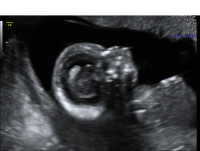

Micrognathia

Micrognathia is a condition where the mandible (jaw bone) is very small. Micrognathia occurs in approximately one in 1,600 pregnancies.